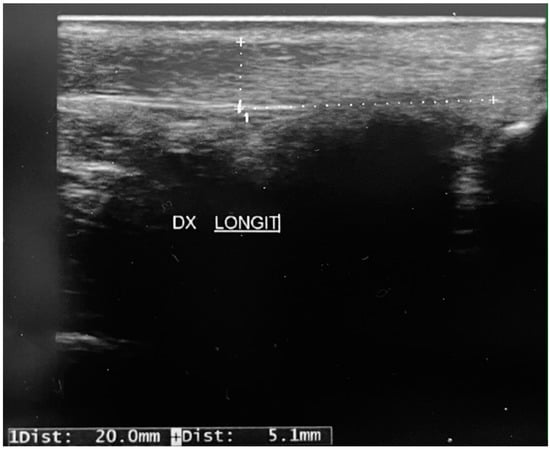

During data collection, one of the patients analyzed in our study suffered a rupture of the right Achilles tendon as she walked (Figure 1). The patient was a volleyball player and she was in good health. She had not taken drugs with a potential negative effect on tendons, such as quinolones or corticosteroids, and she had no extrinsic risk factors for tendinopathy, such as use of inappropriate footwear or overtraining. The ultrasound we previously carried out showed thickening of the Achilles tendon and diffusely hypoechoic superficial areas (Figure 2) 2 cm from the insertion on the calcaneus.

It seems interesting to underline that, in our patient, the finding of the ultrasound alterations corresponding to the site of the rupture could confirm the hypotheses of other authors. The hypothesis could be that the surgical approach to tendon retraction in clubfoot (whether by tenotomy or Z-plasty) is followed by a healing process that restores the continuity of the tendon. However, this process is characterized by haphazard proliferation of abnormal tenocytes, disruption of collagen fibers, and a subsequent increase in the non-collagenous matrix, as observed in tendinopathies [33]. These alterations could represent the substrate on which the sporting overload becomes decisive for subcutaneous rupture.

Figure 2. The ultrasound finding shows a thickening of the Achilles tendon and diffusely hypoechoic superficial areas 2 cm from the insertion on the calcaneus.